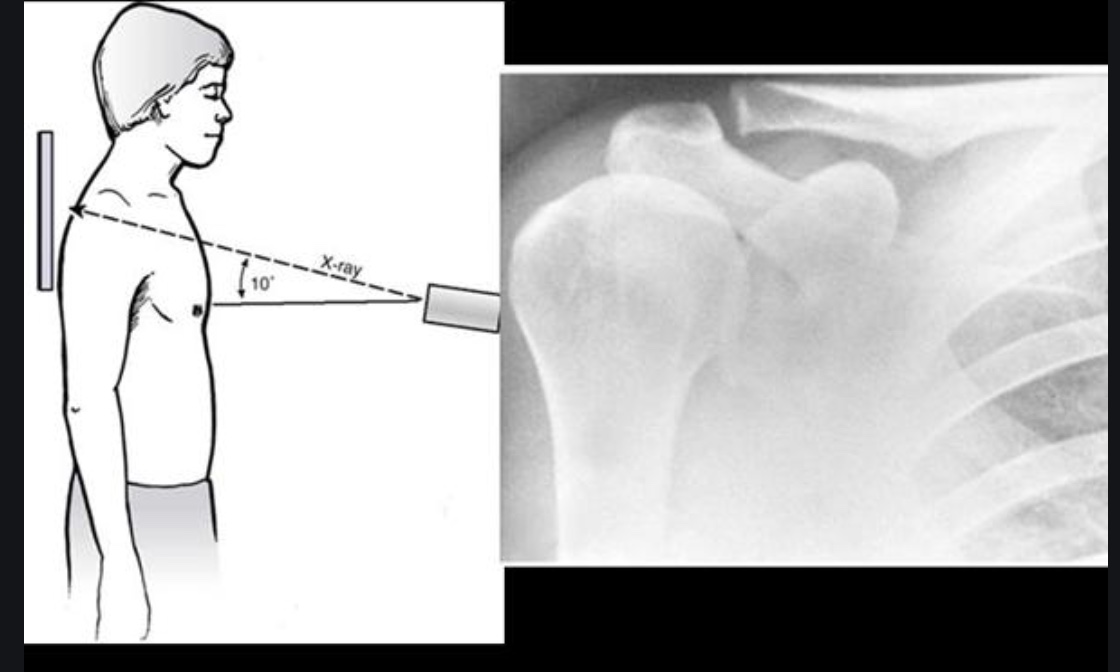

Figure 1 from Management of Displaced Midshaft Clavicle Fractures in Midshaft Clavicle However, the vast majority (~75%; Fractures of the clavicle are common injuries that occur across all age groups but are most frequently seen in the young, active patient population. Diagnosis can be made with plain. Fractures can occur at any part of the clavicle. Clavicle fractures usually occur at the junction (midshaft) between these two curves, most likely because this. Midshaft Clavicle.